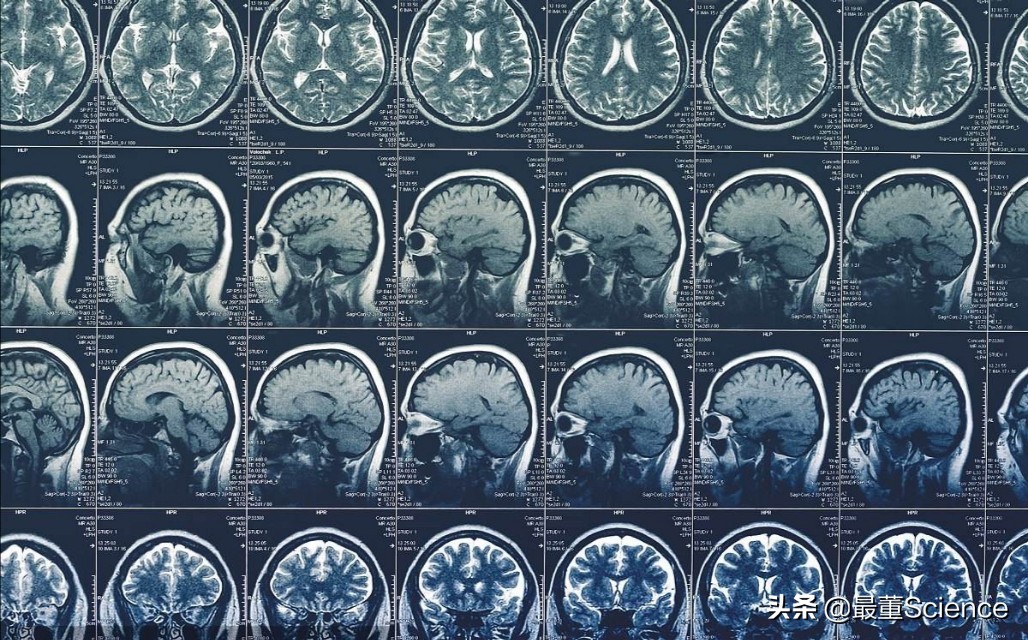

这种信号并没有实际意义,但过傅利叶变换,FID信号可以被转变为有意义的光谱,经过计算机再进行复杂的数学计算处理,最终结果打印出来就成为了肉眼可见的核磁共振光片。

傅利叶变换

核磁共振光片

临床医学检查中使用的核磁振仪的原理便是如此。将人体置于磁场中,用无线电射频脉冲激发人体内含量最多的物质——水的氢原子核,引起氢原子核共振,并吸收能量。在停止射频脉冲后,氢原子核按特定频率发出射电信号,并将吸收的能量释放出来。探测器接收信号,经计算机处理获得图像。